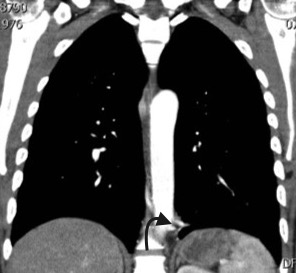

Paciente de 39 años con antecedente de Síndrome de Tolosa Hunt, quien ingresa al servicio de urgencias por disminución de la agudeza visual y cefalea. Dado el antecedente se considera realizar estudios complementarios para descartar enfermedad granulomatosa, como causa del síndrome, encontrando hallazgos incidentales en las imágenes del tórax. El secuestro pulmonar es una anomalía congénita caracterizada por tejido pulmonar displasico, sin conexión normal con la vía aérea, irrigado por la circulación arterial sistémica. Hay dos tipos de secuestros, el intralobar y el extralobar. El intralobar (75%), puede ser congénito o adquirido como secuela de infecciones recurrentes localizadas, está cubierto por pleura del pulmón normal adyacente y generalmente su drenaje venoso es a través del sistema venoso pulmonar ipsilateral. El secuestro extralobar (25%), es considerado una anomalía congénita, está revestido por su propia pleura y su drenaje venoso es sistémico. Tanto el secuestro intralobar como extralobar reciben suplencia arterial sistémica. En los estudios de imágenes, el secuestro se puede presentar como consolidación focal, nódulo o masa, de localización paravertebral, contiguo al hemidiafragma, en los lóbulos inferiores (segmento posterior), con mayor frecuencia en el lado izquierdo (98%) y con una suplencia arterial anómala dada por una o múltiples ramas (15%) generalmente de la aorta torácica y su drenaje puede ser al sistema venoso pulmonar y con menor frecuencia a la circulación sistémica.